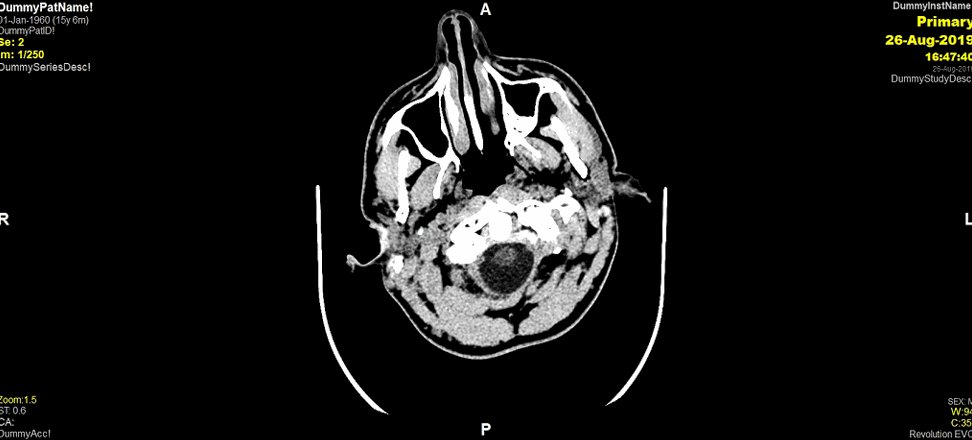

30. The results from the head CT are shown below. What do you see?

31. Good work guys! The CT scan demonstrates progression of the L sided EDH, with midline shift and effacement of the ventricles. As a little reminder here is the first CTH we performed. You can see the rapid progression in the extra-axial collection...

31. On neuro-imaging, extradural haematomas give a biconvex/elliptical/ lentiform shape. Does anyone know why this is? (gif inspired by @AbbieTutt!)

32. Extradural haematoma’s (EDH’s) are extra-axial collections. This means they are external to the brain parenchyma. Because they collect between the suture lines of the cranium, they give this elliptical shape!